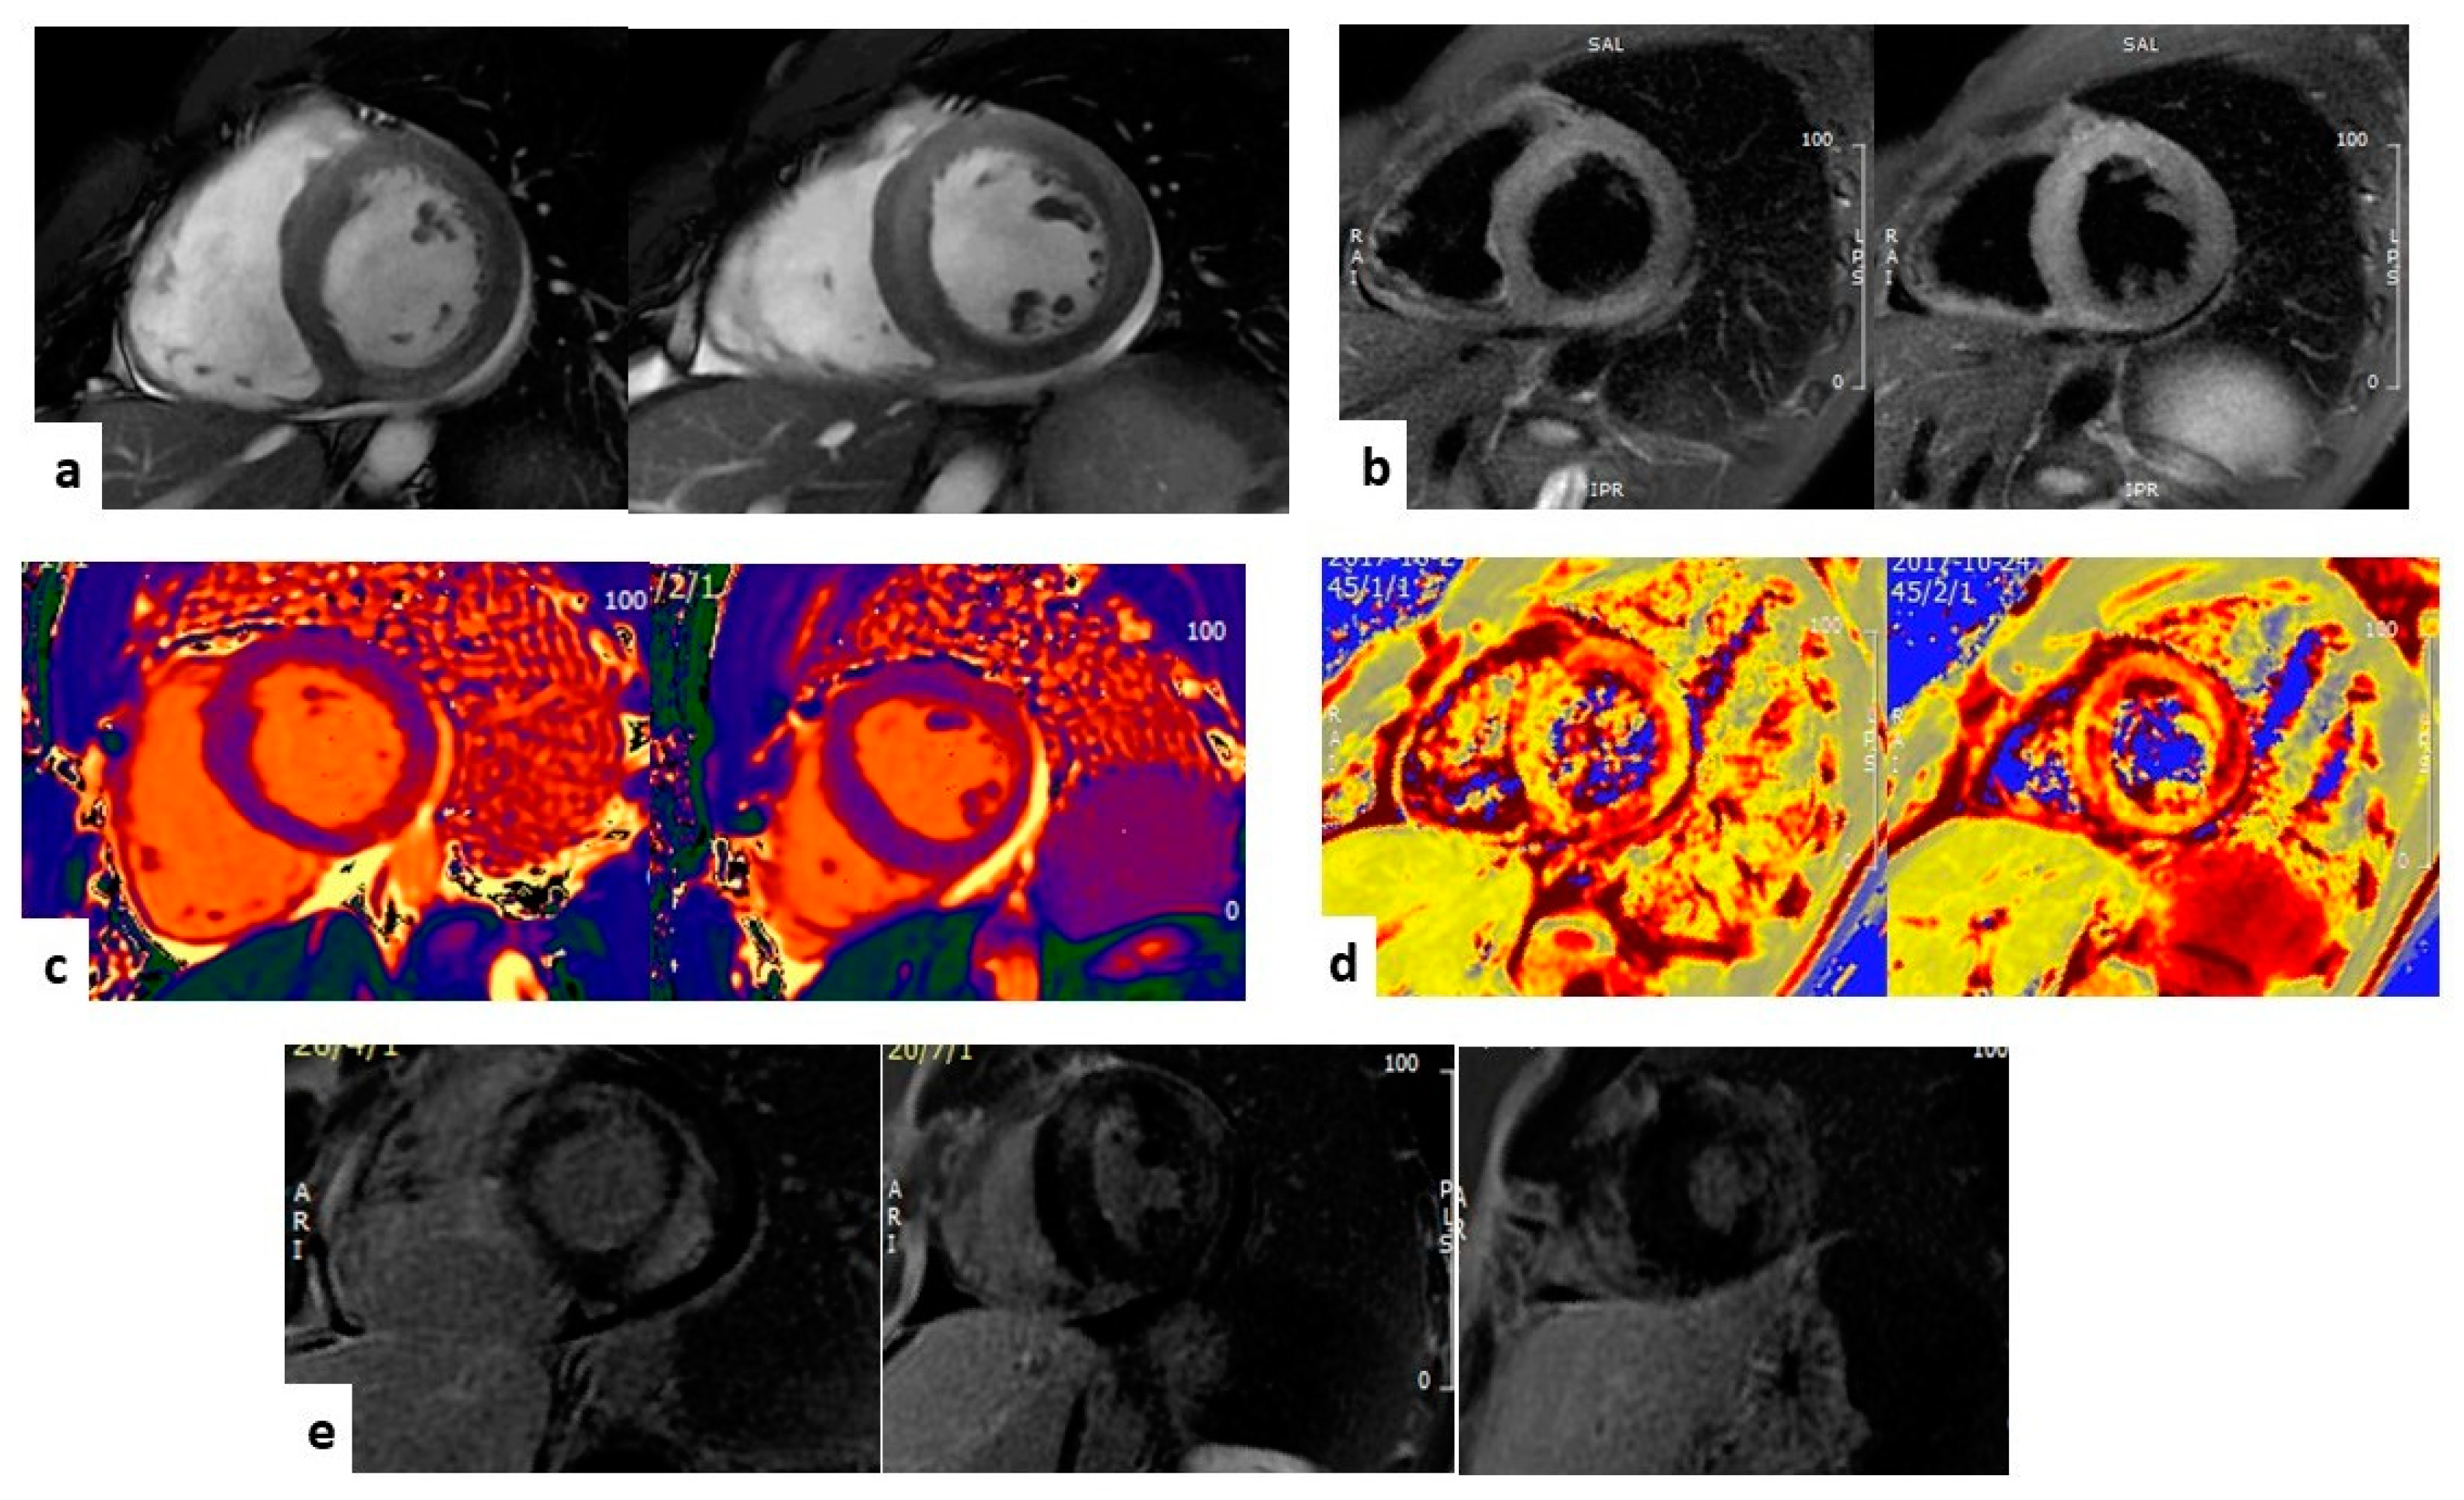

2.1. Morphology and Function

2.2. Tissue Characterization